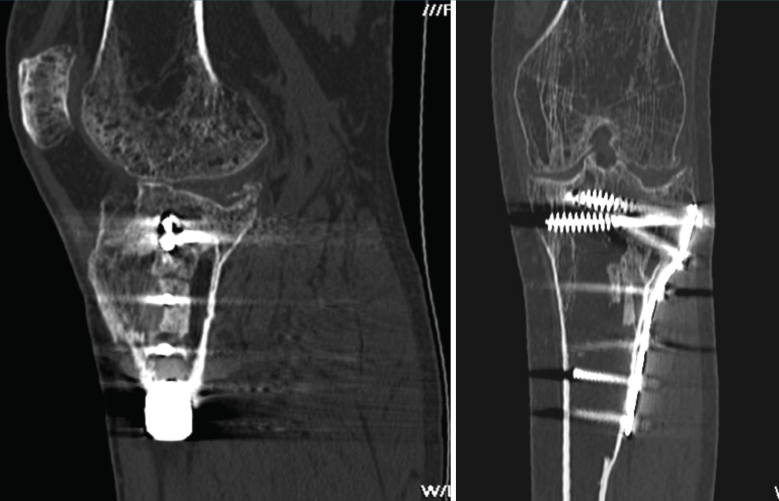

1.2. Tibia (Figura 20)

2. Complicaciones de las fracturas

2.1. Injertos

En las fracturas que requieren un aporte de injerto, la TAC es útil para valorar el porcentaje de su asimilación al hueso (Figura 21).

2.2. Pseudoartrosis

La pseudoartrosis se define cuando, transcurridos al menos 6 meses desde la fractura, no se produce su consolidación y se evidencian muy pocos o ninguno de los signos de evolución radiográfica (Figura 22).

2.3. Retardo de la consolidación

El retardo de la consolidación es un enlentecimiento de la velocidad esperada (de 3 a 6 meses) del proceso de consolidación de una fractura, pero esta llegará a producirse de forma normal y definitiva (Figura 23).

2.4. Consolidación viciosa

Se produce cuando los fragmentos consolidan en mala posición, con deformidades que alteran el eje del miembro inferior (Figura 24).

Figura 21. Corte de reconstrucción sagital y coronal de tomografía axial computarizada de rodilla: fragmentos cálcicos incorporados a la medular tibial diafisaria.

Figura 22. Corte de reconstrucción coronal y sagital de tomografía axial computarizada de rodilla: fractura metafisoepifisaria tibial sin consolidación después de 6 meses.

Figura 23. Corte de reconstrucción coronal y sagital de tomografía axial computarizada de rodilla: fractura de epífisis proximal tibial con puente óseo insuficiente por retraso de la consolidación.

Figura 24. Corte de reconstrucción sagital y coronal de tomografía axial computarizada de rodilla: consolidación viciosa de la epífisis tibial proximal.